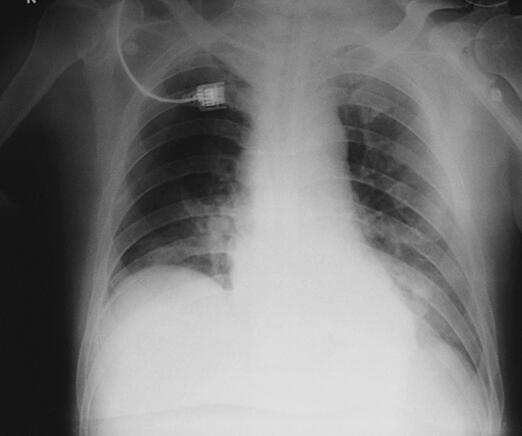

诊治经过:患者入笔者科室后一般情况较差,血压测不出,氧饱和度84%,予以羟乙基淀粉扩容,多巴胺、去甲肾上腺素微泵维持血压,碳酸氢钠纠正酸中毒。立即予以气管插管,呼吸机辅助通气。完善相关检查:CT(图1)结果:①头颅CT平扫未见明显异常;②双下肺肺不张;③双侧胸腔积液;④肝右叶钙化灶。血常规(2月7日):WBC 20.9×109/L,N 94%。心脏彩超(2月8日):左心室舒张末内径61mm,射血分数38%。胸片(图2~图4)诊断:①双侧肺炎;②颈椎术后。先后给予头孢曲松钠和左氧氟沙星、美罗培南和替考拉宁抗感染。因痰培养鲍曼不动杆菌(2月10日),对头孢哌酮-舒巴坦钠敏感,余均耐药,故停用美罗培南,改用头孢哌酮-舒巴坦钠。多次血培养结果提示白念珠菌(2月6日、2月7日、2月9日、2月10日),对氟康唑和伊曲康唑均敏感,因为患者肌酐高,肾功能异常,故给予米卡芬净和氟康唑抗真菌治疗。患者血糖高,2月6日末梢血血糖33.1mmol/L,给予胰岛素强化治疗,但是血糖控制不佳,一直在11mmol/L以上。同时给予化痰、抗炎、保肝、营养神经、调节机体免疫、加强营养、维持内环境稳定、对症支持等治疗。

图4 2月13日胸片

治疗和转归:患者病情曾一度好转,2月10日停用血管活性药物后血压维持在130/80mmHg左右,血常规白细胞计数和中性粒细胞较前明显下降。但患者多次血培养结果提示白念珠菌,痰培养鲍曼不动杆菌,抗真菌和抗感染效果不佳,逐渐出现了多脏器功能衰竭(循环、肺、肾、血液系统)。大剂量血管活性药(多巴胺和去甲肾上腺素)维持下,心率、血压进行性下降,呼吸机吸氧浓度100%,但氧饱和度也只有60%~70%,于2月15日自动出院。